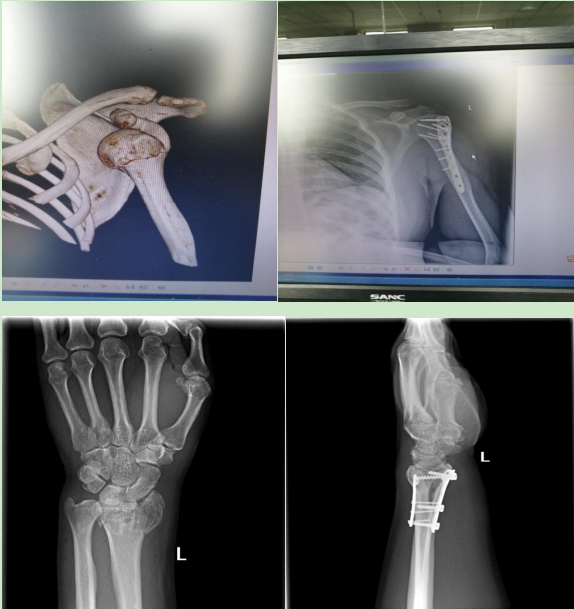

约占住院手术量的50%,项目如下:肩部及四肢骨折的钢板和(或)髓内针治疗,如:锁骨骨折、肩胛骨骨折、肱骨骨折、尺桡骨骨折、掌指骨骨折、股骨骨折、胫腓骨骨折、跖趾骨骨折切开和(或)闭合复位内固定。

关节骨科约占住院手术量的10%,项目如下:髋关节置换术(2019年新技术)肱骨外科颈骨折、尺骨鹰嘴骨折、股骨粗隆间骨折、股骨颈骨折闭合复位内固定、胫骨平台、Pilon骨折切开复位内固定术、Lisfranc损伤切开复位内固定术。老年骨性关节炎关节镜微创手术治疗等。

3.简化JUDET入路治疗肩胛骨骨折。